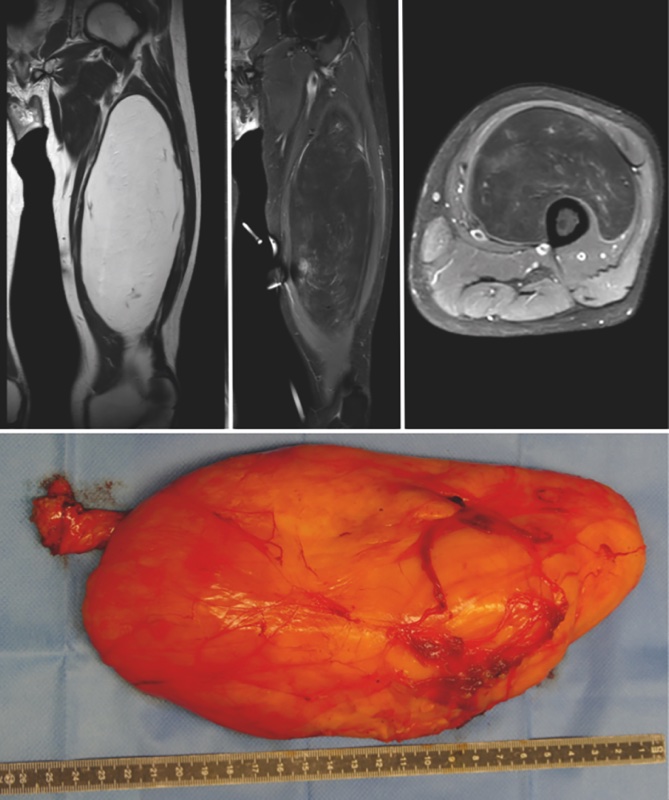

la RMN è più utile nello studio dei lipomi e delle lipomatosi perché consente un’ottima evidenziazione della massa e dei suoi rapporti con i tessuti circostanti, ma soprattutto perché nelle pesature in T2 (FAT-SAT) la massa di un lipoma avrà le stesse caratteristiche del tessuto adiposo sottocutaneo, cioè grandi quantità di acqua, per questo motivo nelle pesature in T1 sono iperintense e nella T2 FAT-SAT sono ipointense. Questa caratteristica è propria del tessuto lipomatoso ed il confronto con il comportamento in T1 e T2 del tessuto sottocutaneo consente di definire con quasi certezza la natura lipomatosa della lesione, inoltre lo studio in T1 e T2 consente di valutare se ha caratteristiche omogenee all’imaging o presenta delle aree differenti cosa che può fare sospettare una lesione lipomatosa maligna o un lipoma atipico cioè un liposarcoma maligno di basso grado o lesione lipomatosa con un’area di ossificazione o sclerosi e/o di dedifferenziazione5

L’esame istologico di un lipoma dimostra caratteristiche di una lesione globosa o lenticolare, nel caso di lesioni superficiali; mentre lipomi profondi assumono forme che sono condizionate dal fatto che crescano all’interno di strutture muscolari circostanti. Il colorito macroscopico del lipoma è giallo, la lesione è in genere capsulata, possono essere delle aree screziate e /o emorragiche, la consistenza è tipicamente elastica molle e il colore pressoché omogeneo. L’istopatologia dimostra cellule adipose mature di forma e dimensioni variabili talora molto più grandi dei normali lipociti. Il trattamento chirurgico consiste nell’escissione marginale 6 (Fig. 1).